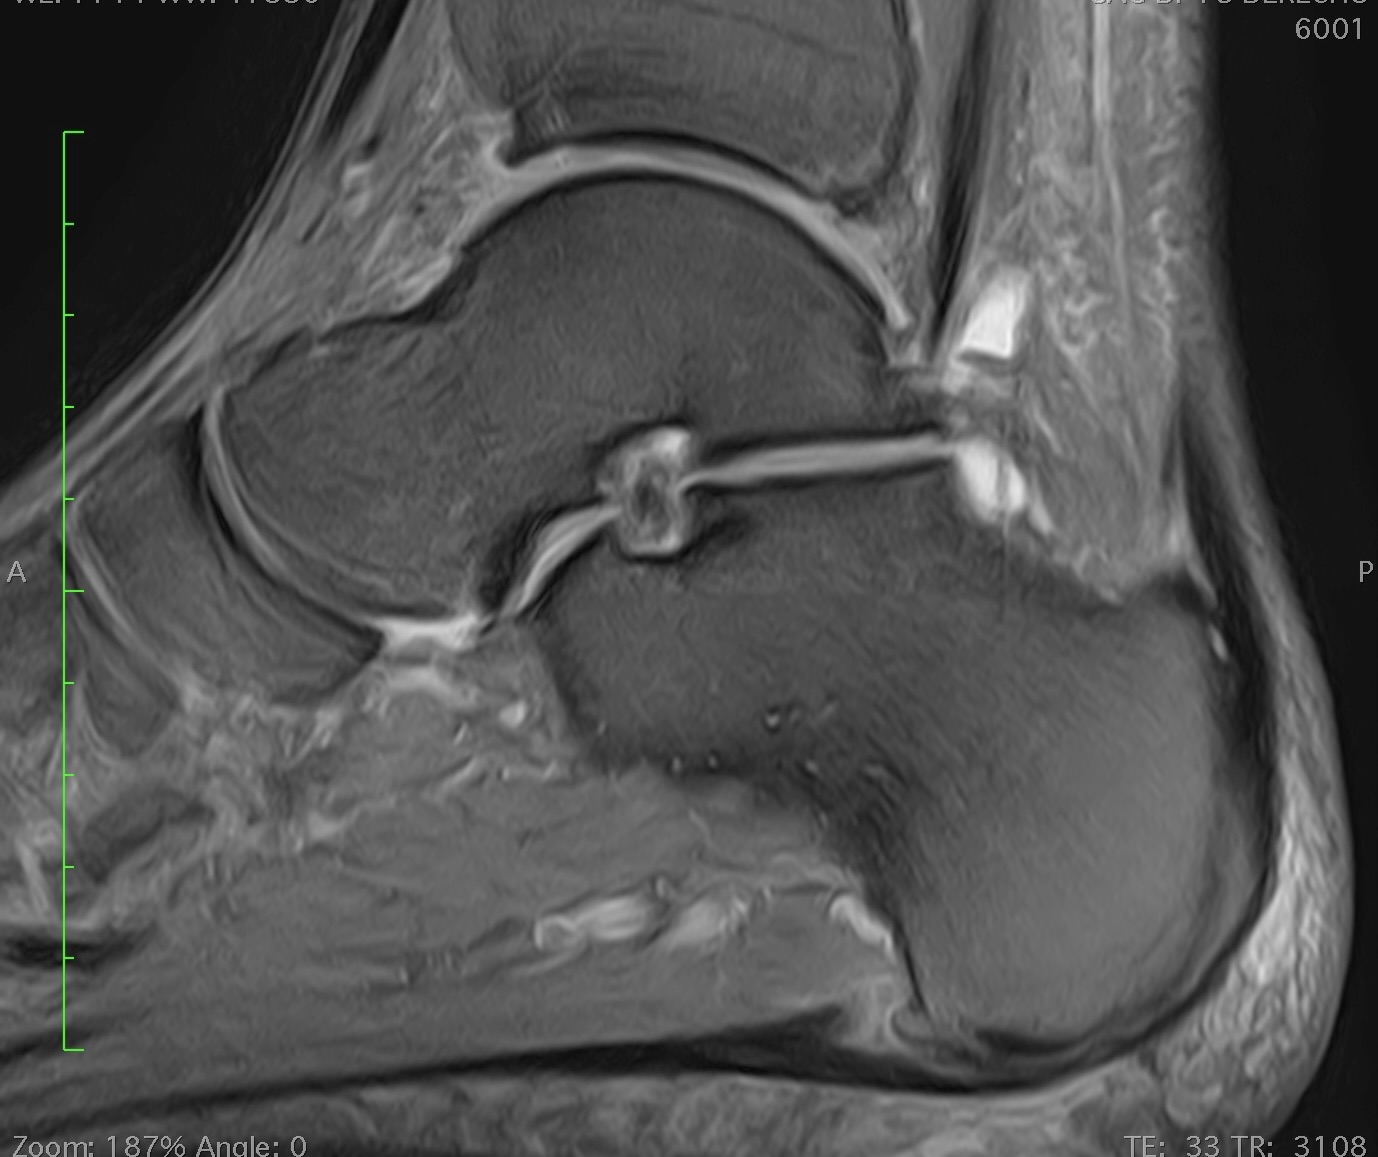

Lesiones osteocondrales

Las lesiones osteocondrales son las que afectan al cartílago y hueso de las articulaciones.

Son frecuentes y especialmente graves las que afectan al astrágalo ya que el cartílago no tiene capacidad por sí mismo de regeneración.

La causa generalmente suele ser un traumatismo aunque muchas veces no es importante, pudiendo desencadenarse por microtraumatismos repetidos (torceduras, esguinces, etc.).

El paciente suele referir dolor en el tobillo, a veces con inflamación y con sensación de fallo o poca estabilidad. Para el diagnóstico es imprescindible una minuciosa exploración, ya que en muchas ocasiones existen factores biomecánicos favorecedores de esta patología, como son alteraciones en el eje del pie o la pierna o inestabilidades por fallo de los ligamentos. El diagnóstico clínico deberá correlacionarse con exámenes radiológicos, de resonancia magnética y/o TAC para aconsejar y planificar el tratamiento más adecuado según cada caso.

Existen diversas técnicas para el tratamiento de la lesión osteocondral, desde la reparación mediante estimulación ósea por microperforaciones, a la aplicación de técnicas avanzadas de regeneración mediante cultivo de condrocitos o de sustitución mediante injerto osteocondral. La indicación de cada una debe ser individualizada según el paciente, la edad, el tamaño y profundidad de la lesión. En ocasiones deberá corregirse además la existencia de una alteración en el eje de apoyo del pie o la reparación ligamentaria.

En nuestra consulta le ofreceremos un enfoque completo, en el tratamiento de estas lesiones y en la indicación de las técnicas más precisas según cada caso.